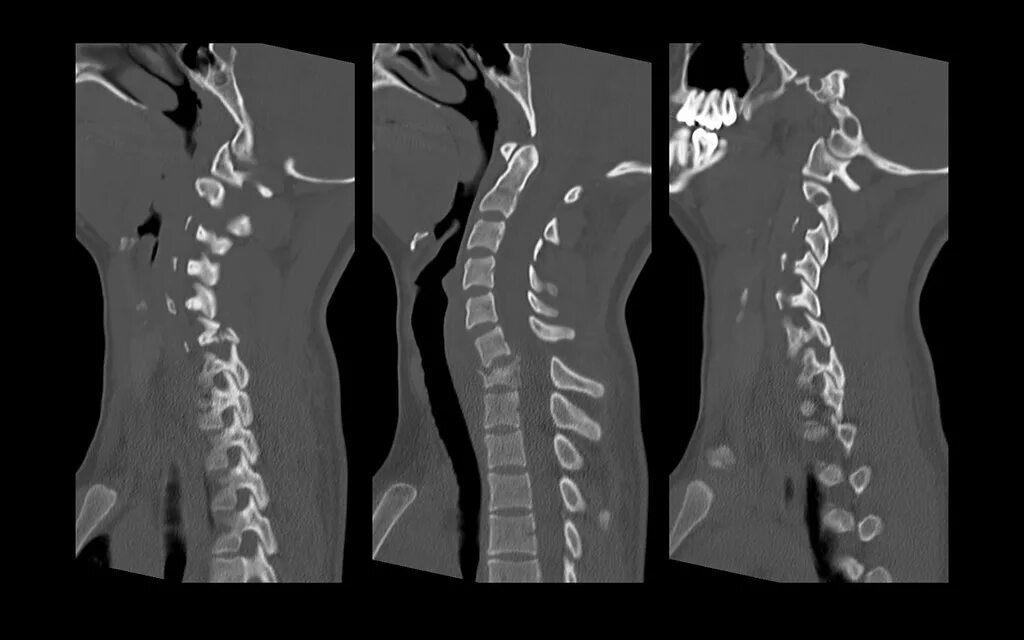

Компрессионный 4 позвонка